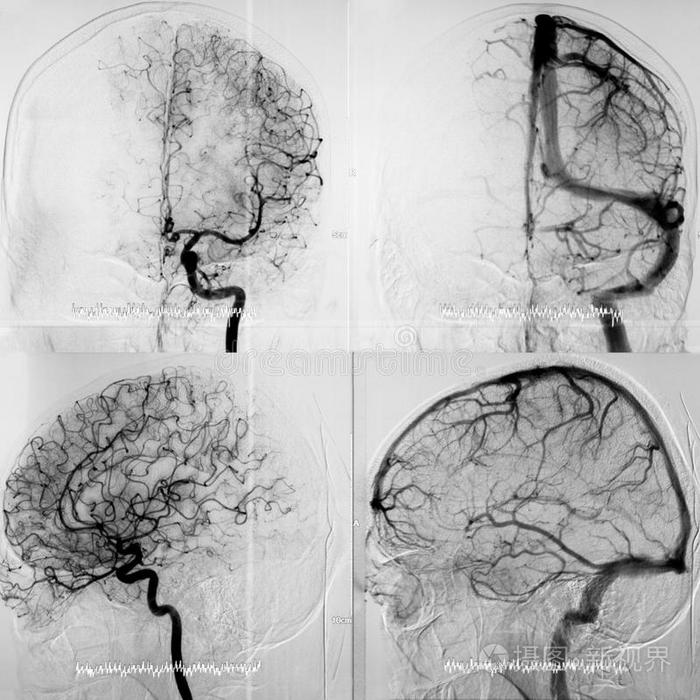

dsa正位显示大脑中动脉,大脑前动脉血流良好

[经验交流]后交通动脉瘤一些dsa图片

头颅循环的dsa两个阶段